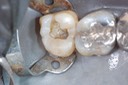

Photos of Clinical Operations

Mentors: Drs. Randy Allan, Greg Card, Peter Kearney

Clubs #44 and #50 joint meeting